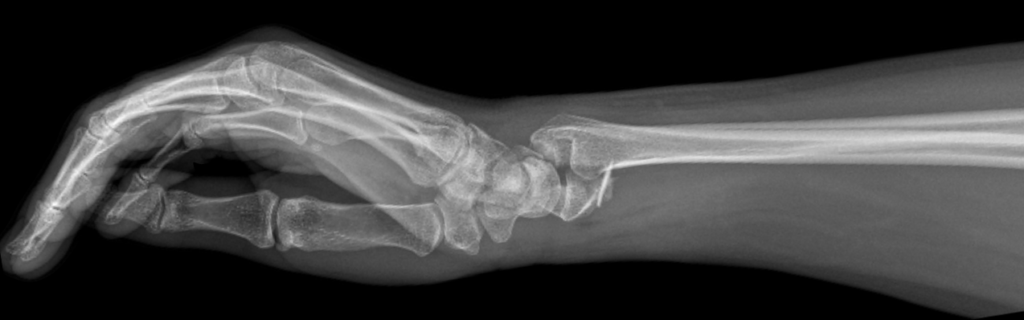

Barton fracture

Barton fracture is an intra-articular fracture of the distal radius with subluxation or dislocation of the radiocarpal joint in the direction of the fracture fragment.

Either the ventral (anterior/volar) or dorsal (posterior) aspect of the radiocarpal joint is fractured. These ‘shear-type’ fractures involve the articular surface of the radius. Barton’s original description delineates the posterior marginal injury (dorsal type Barton fracture) and anterior marginal injury (volar Barton or reverse Barton fracture)